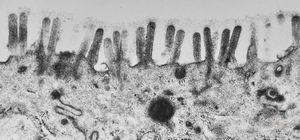

normal mucosa - jejunum - microvilli(anchored core rootlets)

normal mucosa - jejunum - microvilli